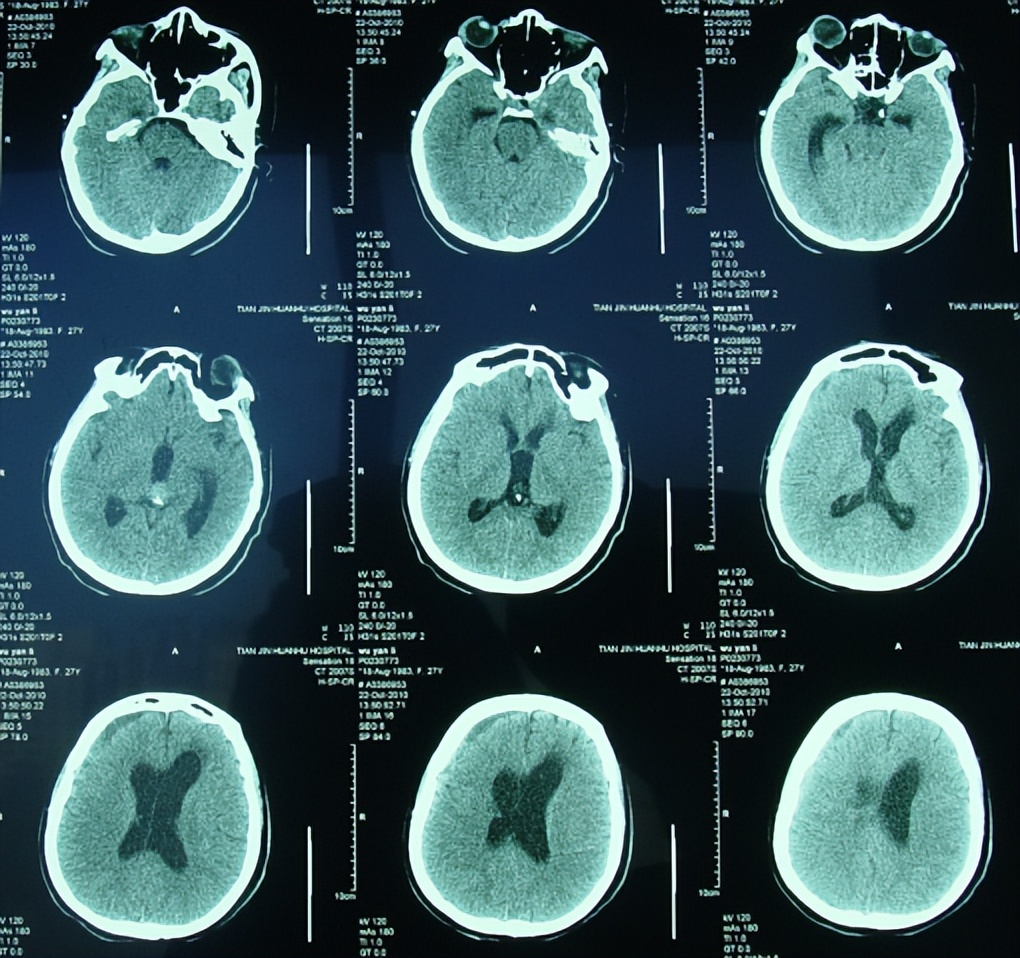

第三脑室ct图片

第三脑室上部层面

看看三脑室有问题吗?

病例分享 | 第三脑室占位

50mm三脑室后部层面 1-侧脑室前角 2-第三脑室后部 3-侧脑室三角区 4

正常颅脑ct表现:三脑室下部层面 表现

图1 ct扫描显示侧脑室和第三脑室脑积水伴室管膜水肿

ct图像显示鞍上区有一个大的不均一的高密度出血性肿块,伴有第三脑室

【求助】第三脑室出血并水肿

第一周,轴位和矢状位平扫 ct 显示第三脑室顶有一圆形结节;侧脑室

2.1日发病时ct,鞍上池及三脑室可见高密度影